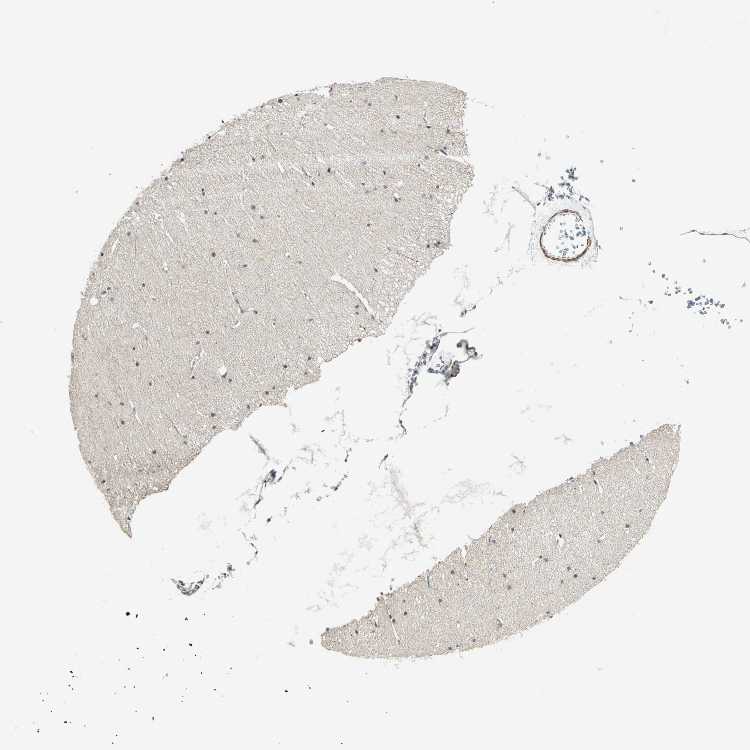

CEREBELLUM - Antibody stainingi

Antibody staining in the annotated cell types in the current human tissue is reported as not detected, low, medium, or high, based on conventional immunohistochemistry profiling in selected tissues. This score is based on the combination of the staining intensity and fraction of stained cells.

Each image is clickable and will lead to virtual microscopy that enables deeper exploration of all samples and also displays staining intensity scores, fraction scores and subcellular localization as well as patient and tissue information for each sample.

Antibody HPA005544Antibody CAB004508

Purkinje cells HighLow

Cells in granular layer -High

Cells in molecular layer LowMedium